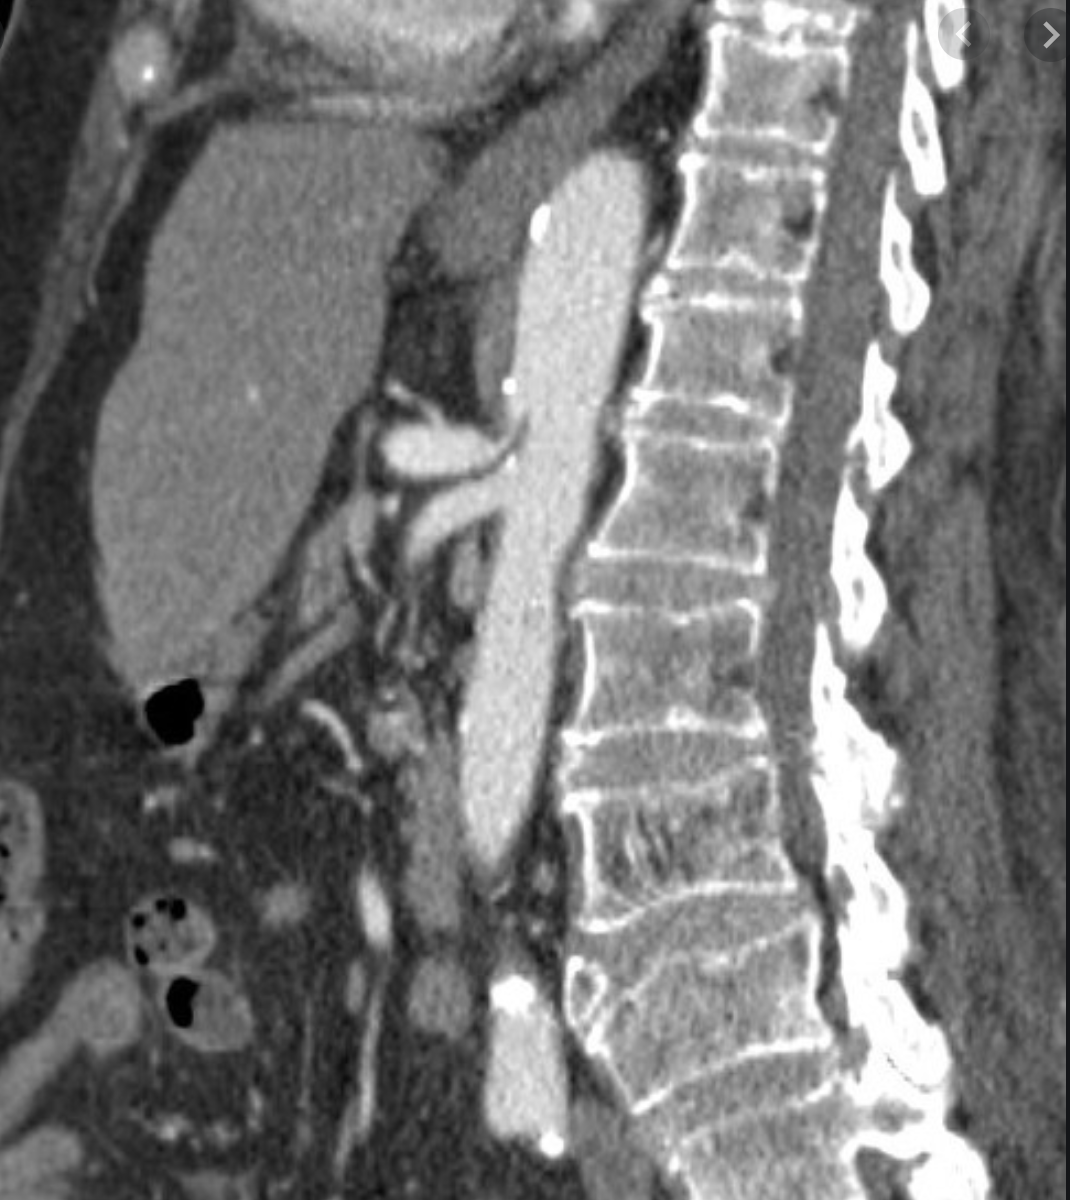

Distal aorta, iliac, pelvic & leg arteries: persistent sciatic artery: